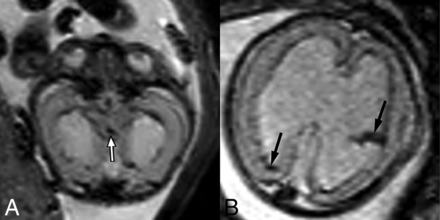

T2-weighted EPI sequences of 2 different fetuses with aqueductal stenosis demonstrating T2-hypointense hemorrhage within the cerebral aqueduct (A) in a 21-week fetus (white arrow) and within the lateral ventricles (B) in a 23-week fetus (black arrows).